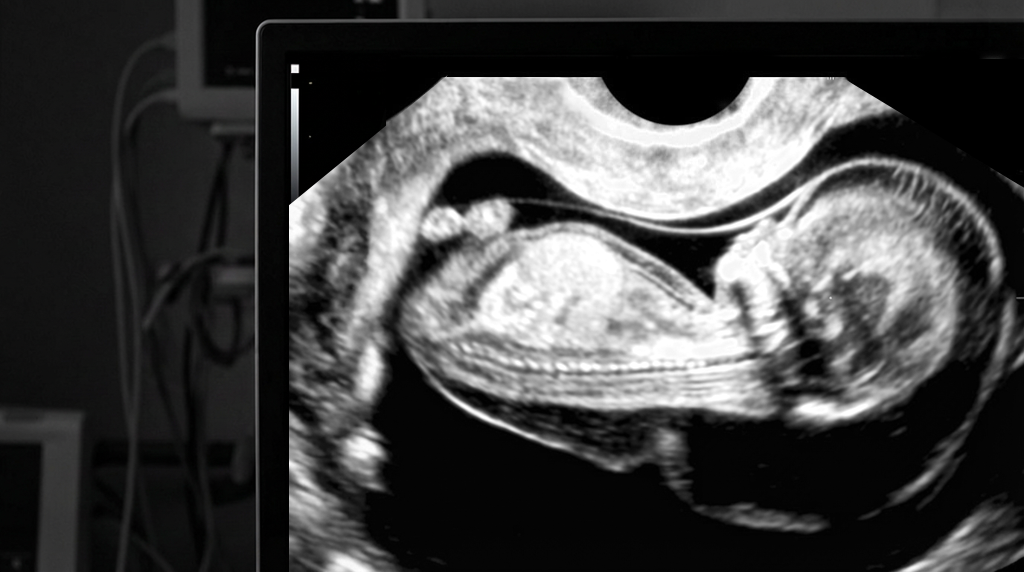

The NT scan is an ultrasound in early pregnancy which measures the thin pocket of fluid at the back of your baby’s neck. This measurement helps estimate the chance of some chromosomal conditions (like Down syndrome) and certain structural problems, especially heart defects.

You lie on the couch and gel is placed on your tummy. The sonographer moves the probe over your abdomen to see the baby on the screen, checks the heartbeat and general development, and then measures the NT at the back of the neck.

Nuchal translucency is the small pocket of fluid at the back of your baby’s neck, measured in millimetres.

The NT scan is the whole ultrasound examination where this measurement is taken, often along with checking that the baby is alive, dating the pregnancy and, in some advanced clinics, having a detailed look at the baby’s structure.